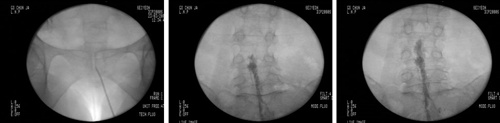

최근 도입된 방법 중 대표적인 것은 감압신경성형술이다. 감압신경성형술은 가느다랗고 긴 특수의료기기 카테터를 이용하여 척추관과 연결되어 있는 꼬리뼈의 작은 구멍들을 통해 척추 신경 부위로 접근한 후 특수 약물을 주입해주는 방법이다. 환부의 정확한 위치에 카테터를 삽입하는 것이 중요한데 시술은 영상증폭장치(C-Arm)를 이용하여 이뤄지므로 환부의 절개 없이도 악물 주입과 조직 분리 과정을 파악할 수 있다.

시술 방법은 두 가지 방법이 있는데 요추 신경공으로 들어가거나 꼬리뼈 쪽으로 도관을 설치한 후 도관을 통하여 기구(카테터)를 넣어 치료 목표 위치로까지 기구를 도달시킨 다음에 주사를 주입하게 된다. 주사약은 염증을 가라앉히기 위한 약간의 스테로이드 성분과 주입 시 통증을 줄이기 위한 국소 마취제 그리고 유착을 제거하기 위한 주사제(H-raze), 부종을 감소시키기 위한 고농도 생리식염수 등을 주입하게 된다. 증상에 따라서 나비 도관을 이용하여 유착이 심한 부분을 기구로 박리하기도 한다.

연세사랑병원 척추센터 허재섭 진료부장은 “하지만 허리통증이 재발하지 않기 위해서는 허리근력을 키워주는 운동치료도 병행해야 한다”며 “근력이 강해지면 외부의 충격이 근육에서 충분히 막아주기 때문에 디스크까지 전달되지 않으므로 감압 신경성형술과 더불어 평소 수영, 걷기와 같은 운동을 열심히 해 허리 근력을 강화시켜주면 추후 발생할 수 있는 재발도 예방하면서 치료효과를 더욱 높일 수 있다”고 조언했다. /강진수 객원기자 osenlife@osen.co.kr <사진> 약물이 병변에 도달하는 내시경 컷.